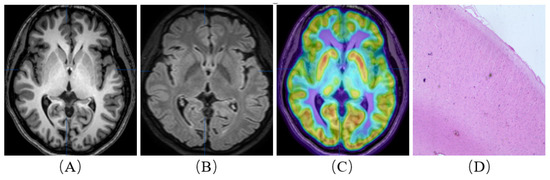

Figure 2.

A patient with refractory epilepsy to drug therapy. He was born in 2003 and was admitted when he was 14 years old. His first seizure occurred at two years old. Interictal and ictal EEG recordings indicated the right parietal occipital lobe region. MRI showed cortical and subcortical signal abnormalities on axial TIWI (A) and FLAIR T2WI (B) in the right parietal occipital lobe. (18F)-FDG PET/MRI images (C) demonstrated hypometabolism in the parietal occipital lobe extending also to the parietal occipital area on the right. Resective surgery was planned for the patient, and an intracranial electrode was not used. Postoperative histopathological examination (D) confirmed ‘type II a, focal cortical dysplasia’. The patient is currently seizure-free (Engel I).